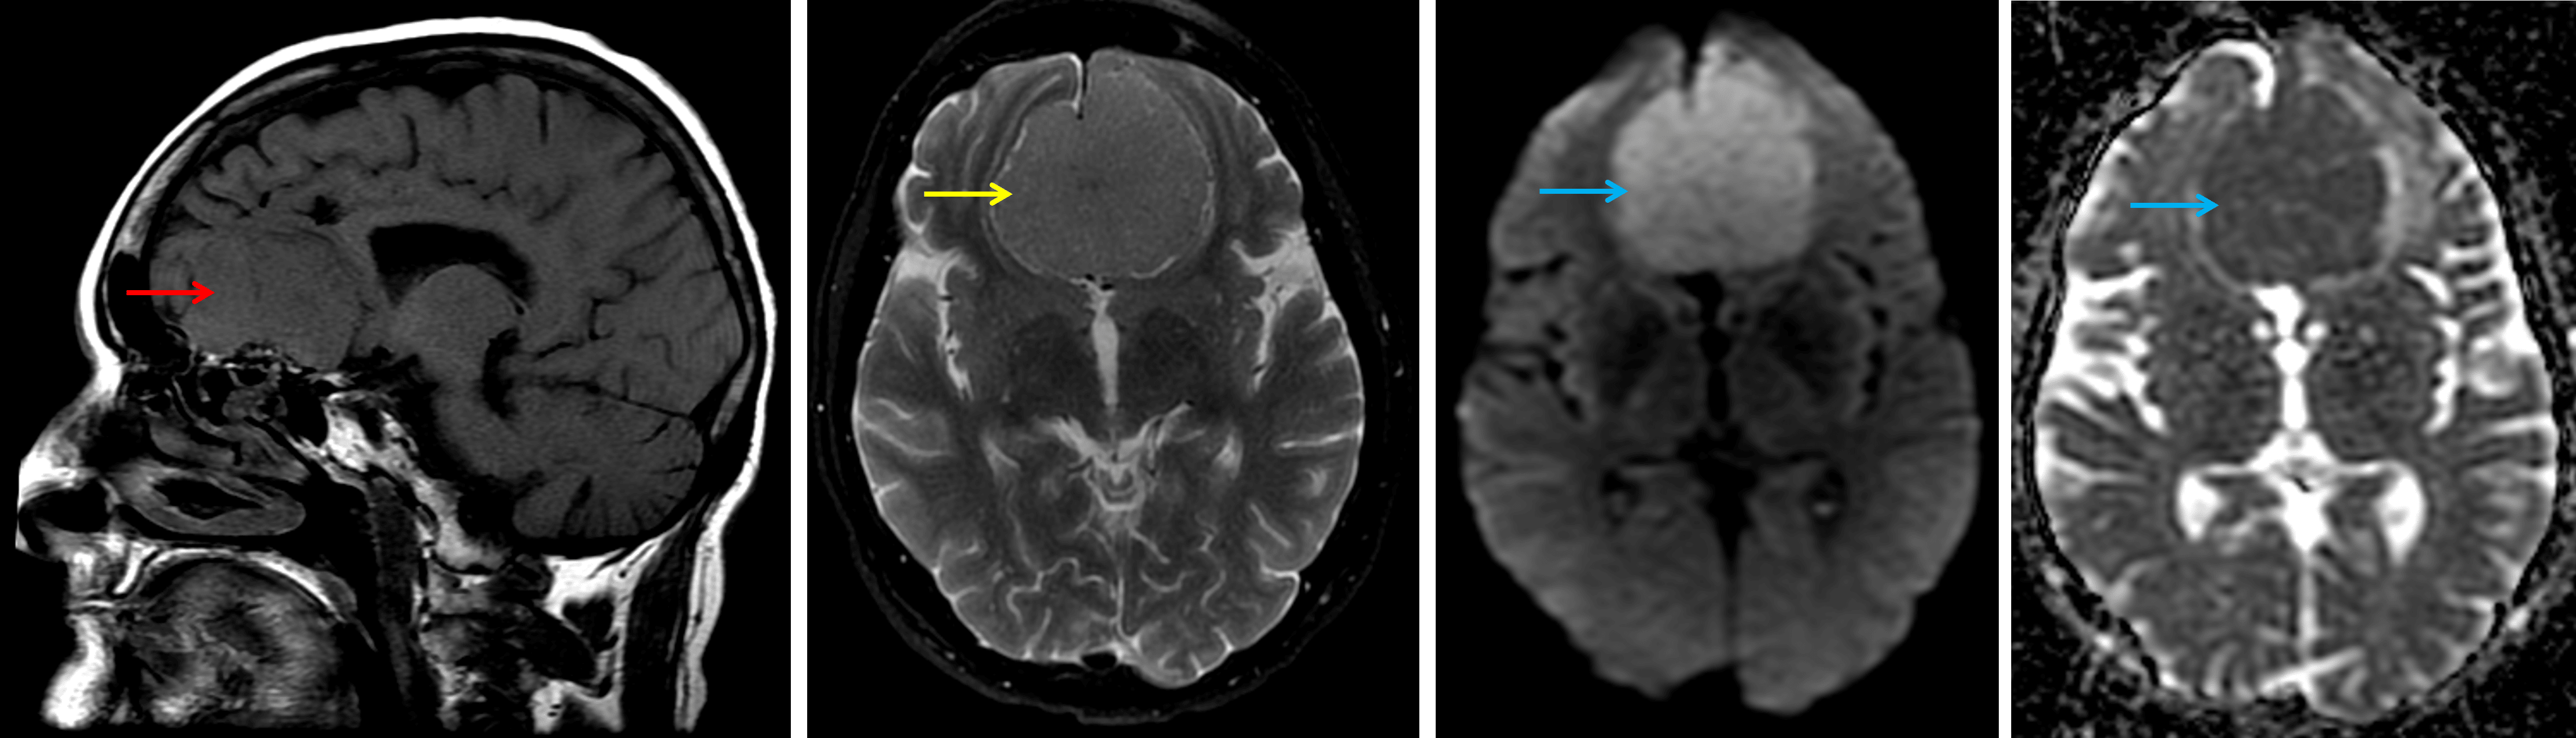

MRI

- T1 hypointense, T2 isointense extra-axial mass centered in the anterior cranial fossa overlying the olfactory groove

- Diffuse enhancement with radiating internal vascularity

- Diffuse internal restricted diffusion

- Areas of susceptibility artifact corresponding with the areas of calcification seen on CT

- T2/FLAIR signal hyperintensity in the adjacent left frontal white matter

Typical MRI appearance of an olfactory groove meningioma, which is relatively isointense on T1 (red arrow) and T2 (yellow arrow) and demonstrates restricted diffusion (blue arrows).